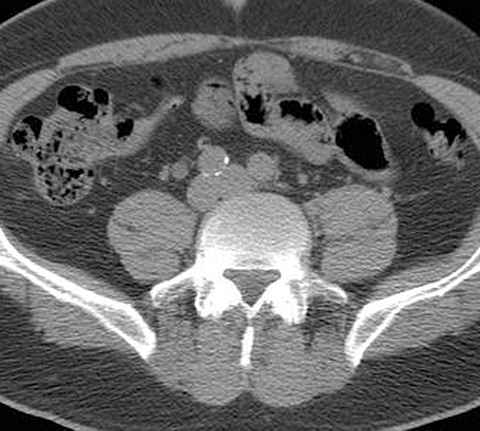

65-year-old male with painless hematuria [2 of 5]